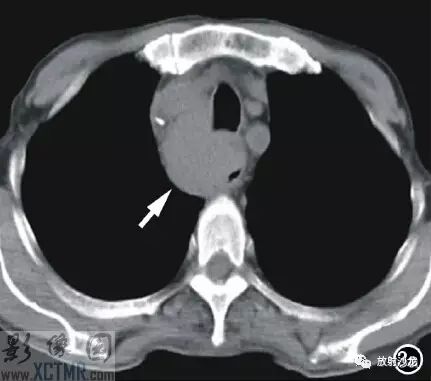

手術(shù)所見(jiàn):腫塊位于食管,約15cm*6cm,上界到喉甲狀軟骨氣管起始處,下達(dá)胸骨后,質(zhì)軟,與食管粘連緊密,周圍無(wú)明顯侵犯,無(wú)法完全切除,行活檢送病理檢查。病理:送檢組織切面呈魚(yú)肉狀;鏡下見(jiàn)腫瘤細(xì)胞彌漫排列,核大,深染,多圓形或不規(guī)則,部分核碎裂,胞漿淺淡,多少不等;免疫組化:S 100(-),HMB45(-),CK(-),CD3(-),CD20(+),CD45RO(-),CD79a(+),CD21散在(+),Mum-1(+),Bcl-2(-),Bcl-6(-)。診斷:(食管)非霍奇金B細(xì)胞淋巴瘤(圖4)。